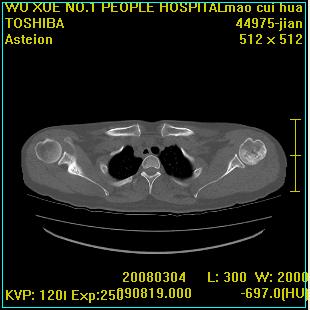

标题: CT12025:男,50岁,左肩活动受限半年。 [打印本页]

标题: CT12025:男,50岁,左肩活动受限半年。

能有x线平片就好了。肱骨头骨结构有破坏。

肩关节骨质破坏呈小囊状,其周软组织轻度肿胀,余未见异常。

考虑:肩袖损伤。建议mri。

左侧肱骨头密度不均匀,高低混杂,周围软组织略肿胀,考虑结核性病变。

考虑左侧肱骨慢性骨髓炎。

左侧肱骨头密度不均匀,高低混杂,髓腔密度稍高,周围软组织略肿胀,肌间隙模糊,考虑慢性骨髓炎可能。密切结合临床!